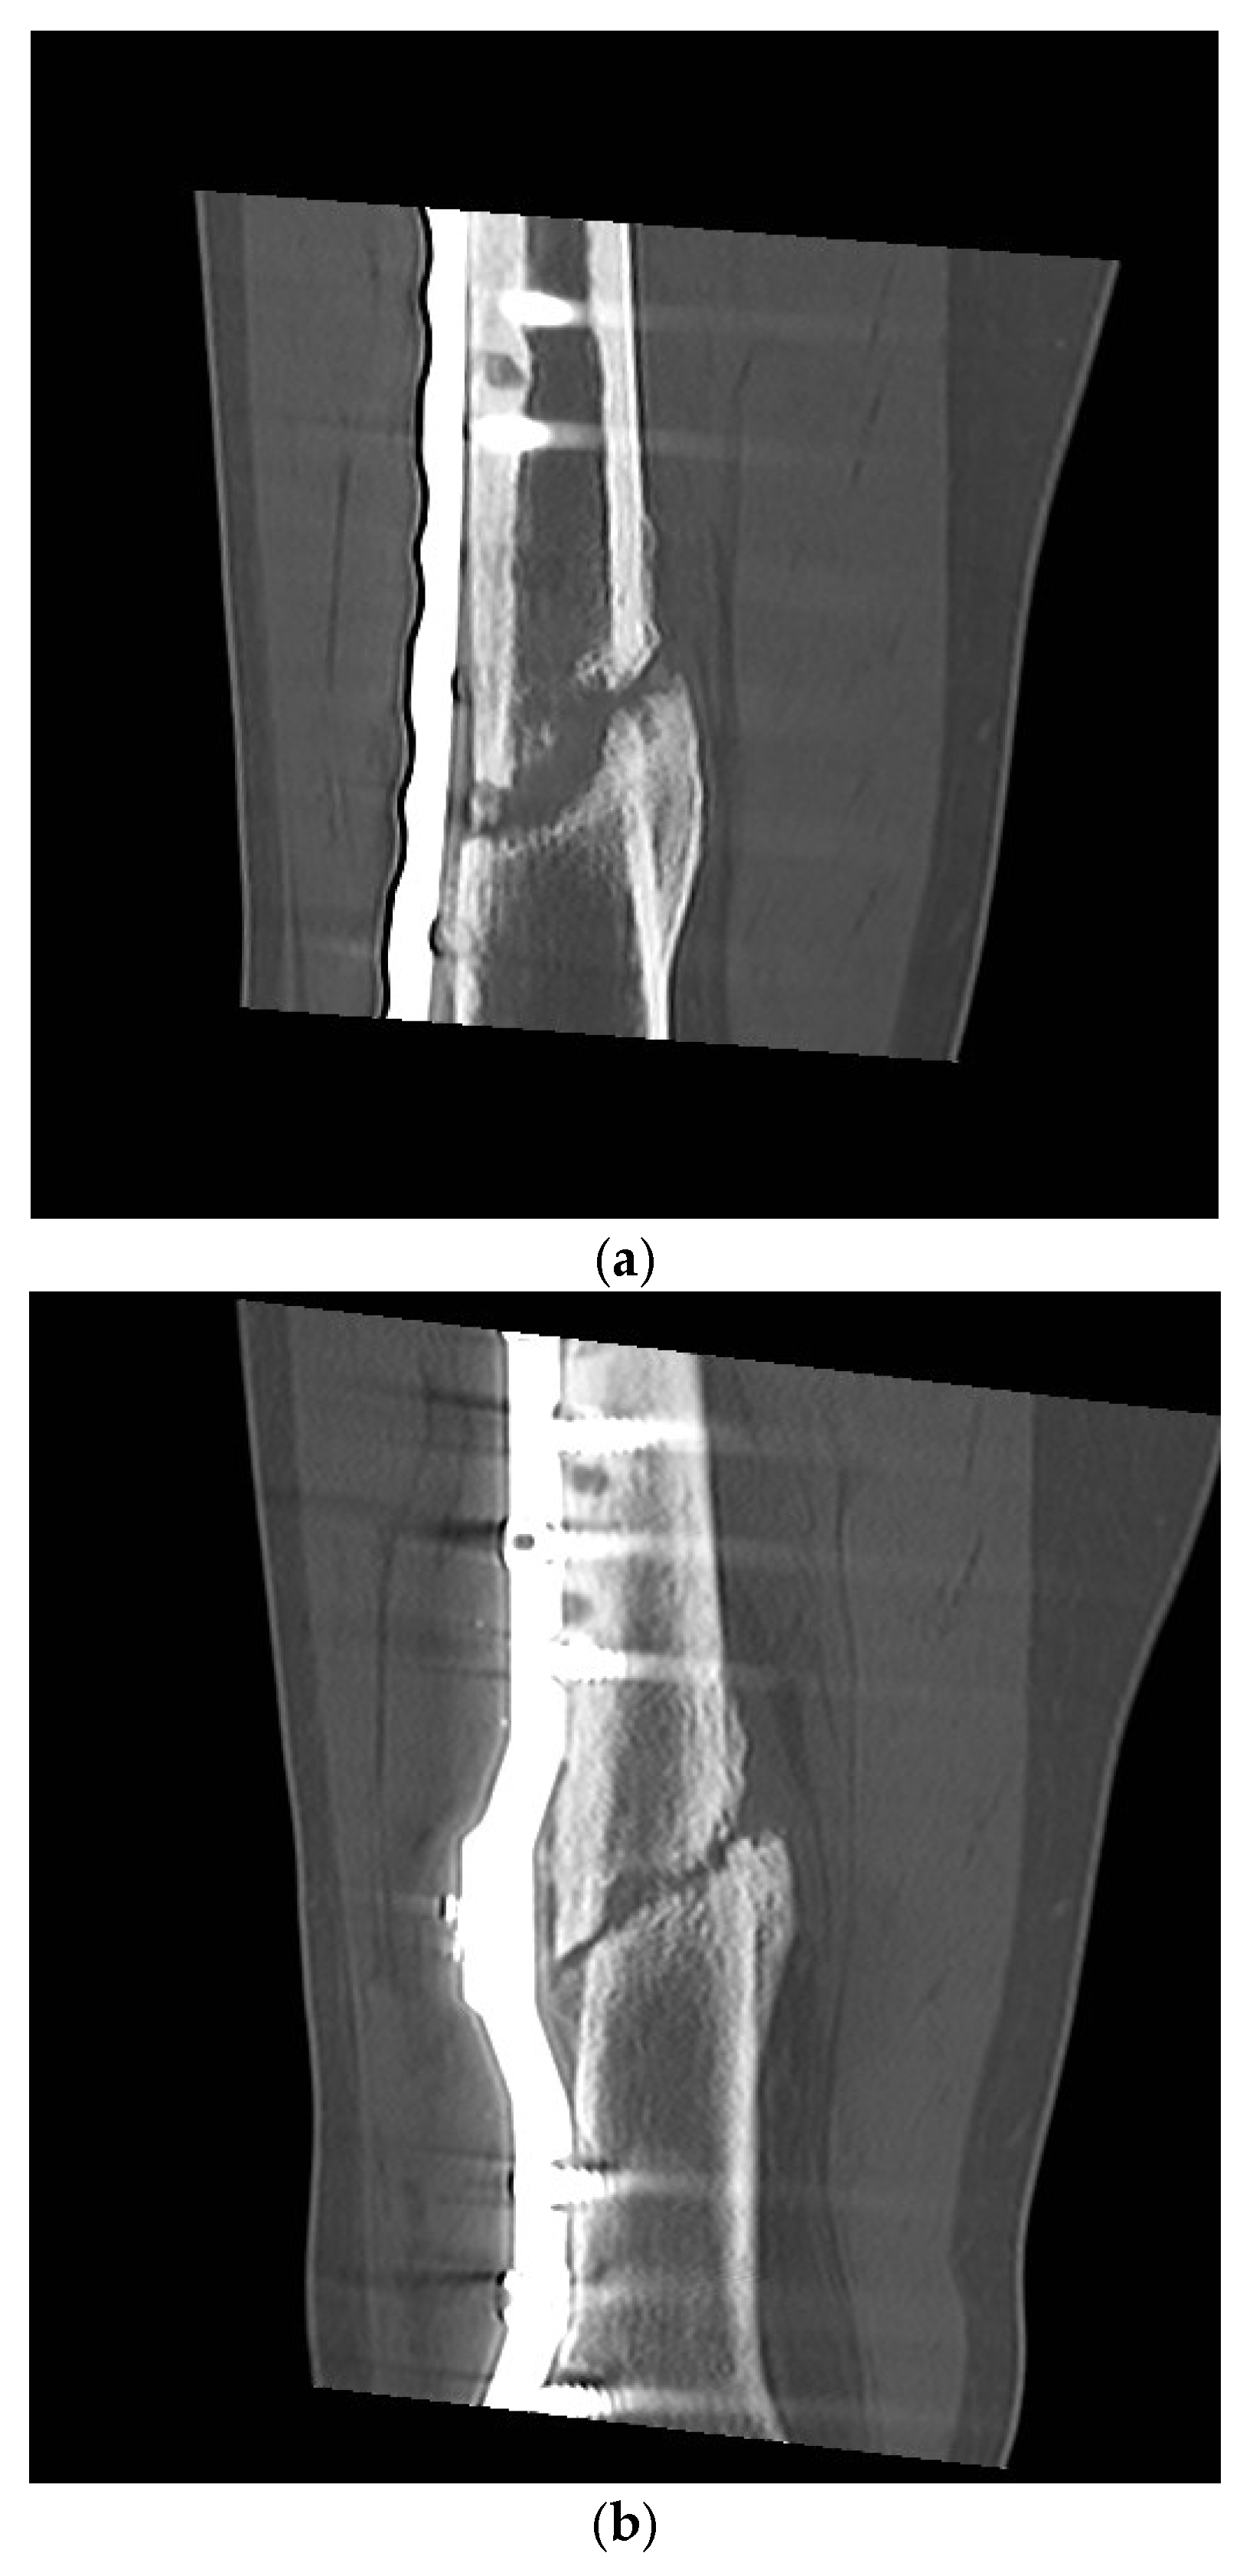

Postoperative Procedure and Further Course